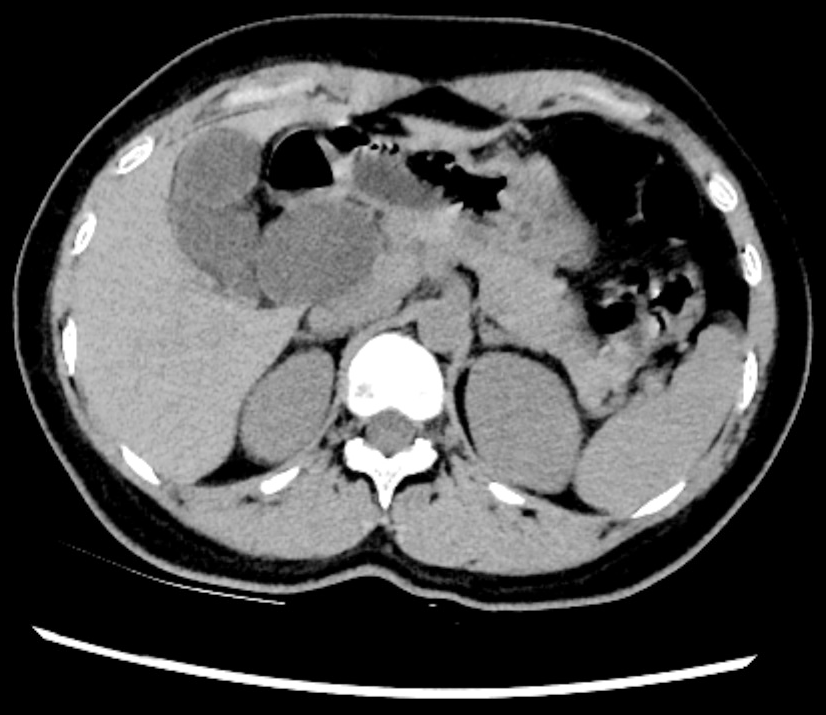

患者陈女士因腹部不适在外院检查发现胆总管异常,来我院就诊。经CT、MRCP等检查确诊为先天性胆总管囊肿(I型),胆总管呈囊柱状扩张,直径达5cm,伴胆汁淤积,考虑到囊肿癌变风险及反复感染可能,肝胆外科团队为其制定了全腹腔镜下胆总管囊肿切除+胆总管-空肠Roux-en-Y吻合术的微创治疗方案。

▲术前增强CT检查图片及报告